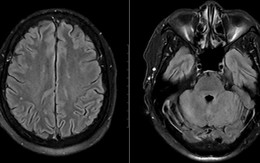

viêm não

Gia tăng căn bệnh dễ lây, ‘tấn công’ vào não: Bác sĩ chỉ cách nhận biết ở giai đoạn mới nhiễm

40 Plus 2026-03-19T17:42:00Căn bệnh truyền nhiễm nguy hiểm này đang có dấu hiệu gia tăng và tiềm ẩn nguy cơ bùng phát trong cộng đồng.